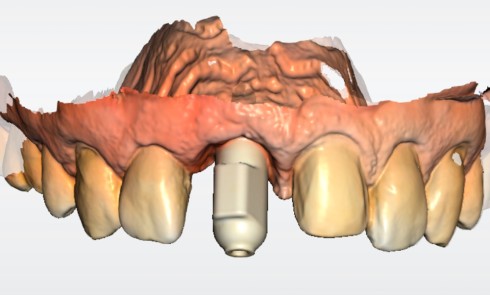

Une patiente de 64 ans, en bonne santé générale, suivie en maintenance parodontale depuis sept ans (parodontite 3B), est vue en juin 2014 pour l’extraction de sa 24 en raison d’infections endodontiques récurrentes. Le plan de traitement prévoit la pose extemporanée d’un implant et sa restauration prothétique quatre mois plus tard. La 25 est une dent couronnée et 23 et 26 sont des restaurations implantaires (fig. 1a à c). La dent antagoniste 35 est une restauration implantaire.

La radiographie péri-apicale au long cône confirme, sur la 25, un élargissement desmodontal, notamment en distal, des niveaux osseux mésio-distaux réduits par rapport aux clichés de contrôle précédents (les radiographies sont réalisées avec une technique parallèle avec des angulateurs de Rinn non personnalisés), un apex radiculaire normal et des niveaux osseux stables sur les implants adjacents (fig. 5). Le cisaillement systématique du fil dentaire lors de son passage confirme des points de contact très étroits entre 24, 25 et 26.